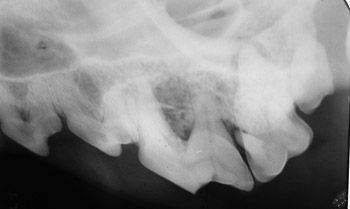

Dental disease is a progression of changes. First, plaque builds up on the teeth. This turns into tartar, or calculus, over time. The tartar, especially under the gum line where you cannot see it, causes the gums to become inflamed (gingivitis). If gingivitis is left untreated, periodontal disease develops, which results in receding gum lines, infected gums and loose, painful teeth. The associated mouth infection can cause serious illness, as the infection can spread through the blood stream to the heart valves, lungs and kidneys.

The doctors and technicians at Front Range Animal Hospital are experienced in dental care, performing hundreds of dental procedures annually. A thorough dental cleaning requires a light general anesthesia, as it takes 30-60 minutes and includes cleaning off the tartar below the gum line where it is causing damage. After the teeth are clean, their surfaces are polished to make them smooth. A thorough exam is done by the doctor and sometimes dental x-rays are taken. Any teeth that are loose, eroded, or abcessed should be extracted. These teeth will never be normal again and are causing much pain. Any other issues, such as gum lumps or tumors, are addressed. After the professional dental care, you will be instructed on things that you can do at home to help keep your pet’s teeth healthy.